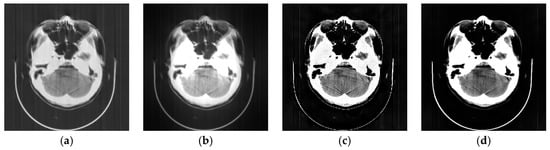

3.2. Head Phantom Experiments